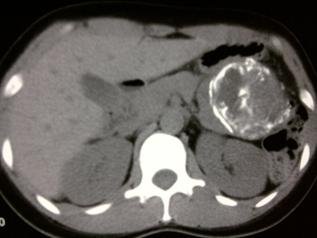

In combination with clinical findings, radiological features of SPT may help to make the correct diagnosis and differentiation from other pancreatic neoplasms. Abdominal ultrasound and CT scan usually demonstrate a huge, well-encapsulated mass with both solid and cystic components and displacement of nearby structures.15,17 Additionally, CT can play much more important role by providing further information about the size, location, the local invasion and vessel involvement of SPT, ultimately help to provide the final treatment strategy. In this study, on pre-contrasted CT, solid and cystic structures were demonstrated in 7 patients with SPT. After enhancement, solid and cystic structures were shown in 11 patients. Especially, the solid portions were moderately or obviously enhanced whereas the cystic parts remained unenhanced (Fig.1), which were consistent with those reported previously.9,11,18 It was mentioned accompanying CBD dilation and intra tumor calcification were infrequent findings in SPT patients.9,11,15,19 In our study, only one SPT patient with a tumor located in the pancreatic head presented with dilation of CBD. Of note, internal or capsular calcification was shown in 5 patients (Fig.2), suggesting the role of calcification on the development of SPT might need to be further investigated. Considering the superiority of MRI in terms of correlation between radiological and clinicopathological findings in SPT, MRI was strongly proposed for the diagnosis of SPT.6,10,18 Consistently, in our study, the diagnosis of SPT suggested by MRI was ultimately confirmed pathologically.

Fig 2

The CT scan indicated the typical internal or capsular calcification in the SPT.